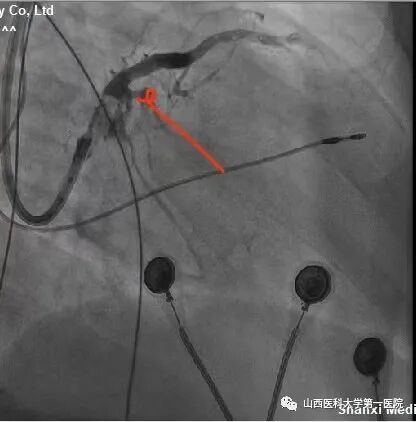

该患者为老年女性,主因反复间断胸闷10余年,加重1周入院。完善相关检查后提示:窦性心律,QRS波宽度187ms、完全左束支传导阻滞形态;心脏彩超显示:左室射血分数:25%,  左室舒末内径:72mm,符合ESC2021CRT指南I类适应证。术中,冠状窦静脉造影发现左室电极靶静脉(左室侧静脉)迂曲,双导丝导丝(Runthrough NS和Pilot50)均无法通过,采用逆向导丝技术,从后静脉逆向进入迂曲的静脉分支及侧支,成功进入左室侧静脉。

该患者冠状窦静脉侧支迂曲严重,前向无法进入左室侧静脉;同时,后静脉逆进入左室侧静脉的分支也非常迂曲,并且多处位置有膈神经刺激,左室电极多次调整,进入不同分支,并调整深度,最终寻找到起搏阈值好且无膈神经刺激位点。赵志强主任医师团队创造性的把冠脉PCI技术应用到手术中,并克服诸多困难,成功完成CRTD植入,期待患者后期心衰症状改善。